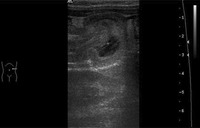

Colecistite: ultrassonografia de colecistite aguda e presença de cálculos biliares

Do acervo de Dr. Charles Bellows